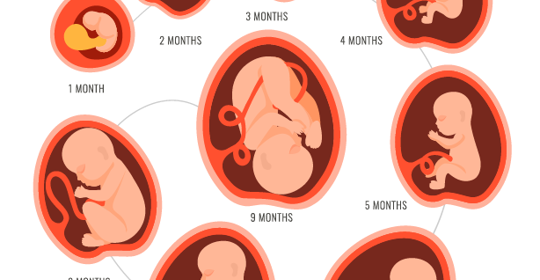

懷孕初期易餓:影響與處理方法